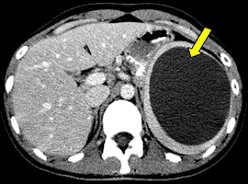

Первичные и метастатические опухоли печени имеют

вид округло-овальных узлов пониженной плотности, хорошо накапливают контрастное

вещество. Определенные трудности вызывают случаи дифференциальной диагностики с

гемангиомами печени, внутривенное контрастирование при этом является

обязательным техническим приемом. Липомы имеют отрицательные значения плотности

и не пересекаются с другими предположениями.

КТ печени КТ киста селезенки